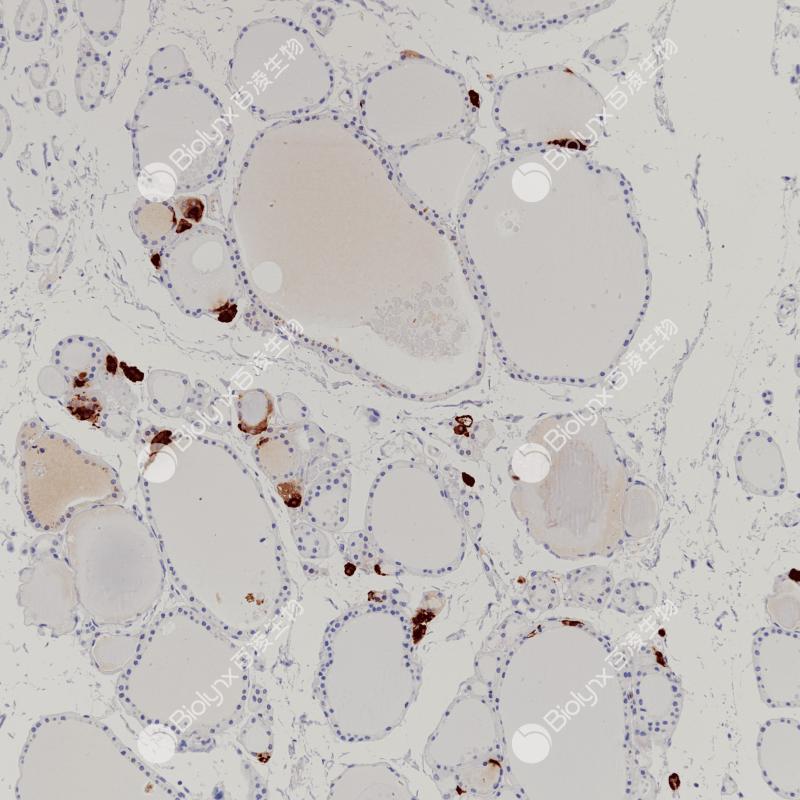

GCDFP-15即gross cystic disease fluid protein 15,是泌乳素诱导蛋白家族中的一员。GCDFP-15抗原可表达于非肿瘤性浆液性涎腺腺体、精囊和乳腺以及乳腺囊肿液等中,可作为乳腺癌标记物。该抗体主要用于乳腺癌的诊断,也常与mammaglobin 联用以判断乳腺癌微小病灶的转移情况。

阳性对照

乳腺癌